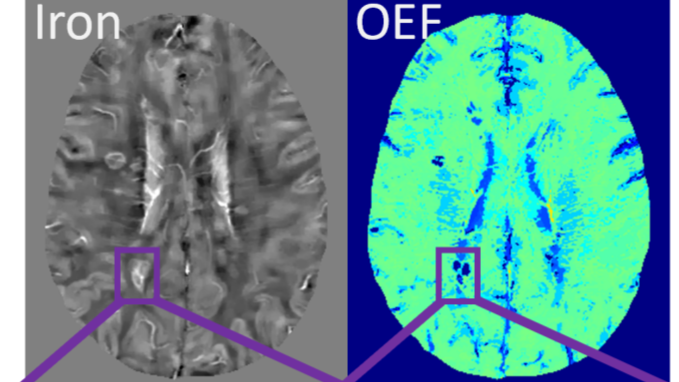

UB Awarded $1.77 Million Grant to Create Tool Set for Oxygen Metabolism Mapping

Posted in Member Research & ReportsTagged For Friday Letter June 07 2024, University at Buffalo

Vanderbilt Research Team Awarded $1.8M from NINDS to Conduct Research on Multiple Sclerosis Biomarkers Using Advanced Imaging, Says Reynolds

Posted in Student & Alumni AchievementsTagged For Friday Letter June 07 2024, Vanderbilt